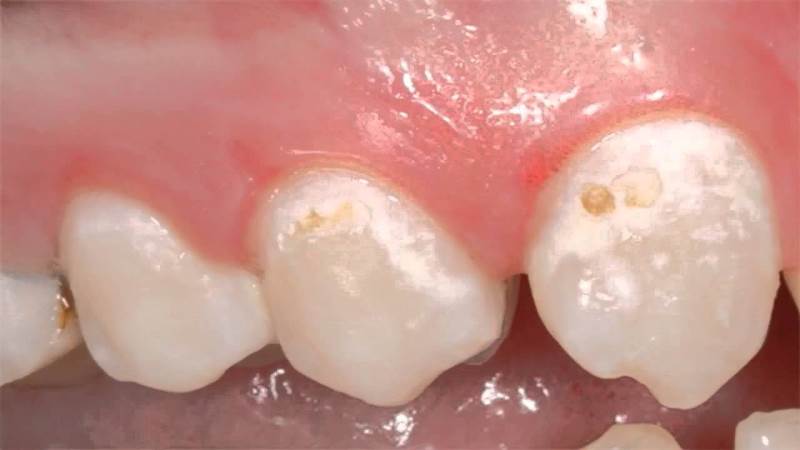

- Кариес на начальной стадии проявляется белыми пятнами. Лечение может проводиться без использования бормашины с помощью реминерализации и фторирования. Эмаль в пораженной области становится мягкой и шероховатой, и если не предпринять меры, пятна могут потемнеть и углубиться, переходя в более серьезную стадию кариеса. Чаще всего такие образования возникают на пришеечной и боковых поверхностях зубов.

- Гипоплазия подразумевает наличие белых пятен как признак врожденного дефекта, который может быть вызван проблемами в период эмбрионального развития. Причинами могут быть токсикозы во время беременности, родовые травмы или инфекции. Если у ребенка появляется белое пятно на зубе, это может свидетельствовать о нарушении обмена веществ или недоразвитии. В молочном периоде такие образования чаще всего наблюдаются на передних зубах. Гипоплазия делает зубы более уязвимыми, поэтому необходимо проводить защитные процедуры с использованием специальных средств. Стоматолог может определить возраст нарушения эмали по расположению пятен.

Гипоплазия может проявляться по-разному: от появления диффузных полос и затемнений до поражения одного или нескольких зубов. Причиной таких повреждений может быть ортодонтическое лечение, при котором скобы препятствовали контакту зубов со слюной, необходимой для минерализации.